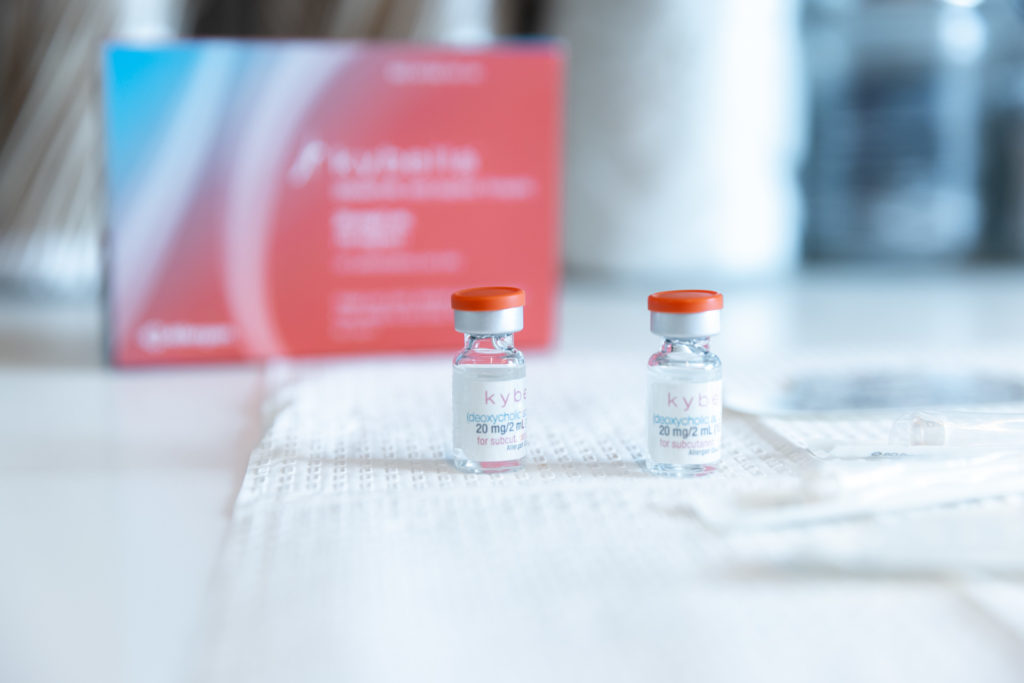

Body Sculpting

- Non-Surgical BBL